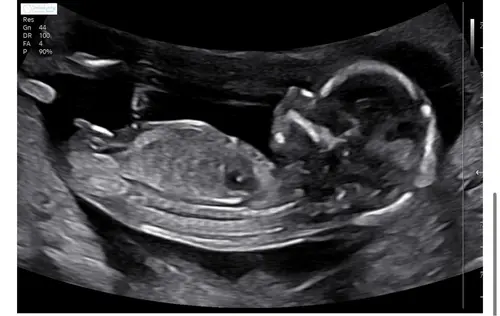

15+3 鉂わ笍

Net de 14 weken echo gehad. Wat denken jullie wat het is ?